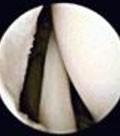

Tratamiento quirúrgico… • INDICACIONES: • Si sintomas persisten a los 3 meses de tto. Conservador • Perdida progresiva de la funcion del hombro • debilidad REPARACION QX: RUPTURA PARCIAL ARTROSCOPIA

Indicaciones artroscópicas.. • Ruptura parcial del manguito • Minimo trauma a tejidos blandos • Rehabilitación mas precoz • Menos complicaciones

Artroscopia